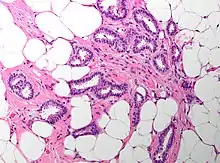

The microscopic histopathology of ICCB tumors stained with hematoxylin and eosin shows cribriform areas covering more than 50% of the tumor with the remaining tumor areas showing tubular and/or other histopathological patterns. The cribriform areas consist of small-sized cells with amphophilic (i.e. taking up both the hematoxylin and eosin stains) cytoplasm, indistinct cell boundaries, and small-to-medium sized nuclei that are surrounded by a sharp nuclear membrane and contain finely stippled chromatin (i.e. DNA coated with protein).[17] Numerous open spaces and/or sieve-like small holes lie between these cells (see above photomicrograph) to give the lesions a Swiss cheese-like appearance. The spaces and holes may contain microcalcifications and/or mucins (i.e. high molecular weight, sugar-linked proteins normally produced and secreted by the mammary gland and found in milk).[3] The cells around these spaces and holes sometimes have "apical snouts", i.e. small protrusions on the side of the cells that faces the spaces and holes.[11] Tubular areas (see adjacent photomicrograph of a tubular carcinoma) consist of well-formed tubules lined with mostly normal appearing tubular cells.[17][20] The other histopathological patterns that may occur in these tumor types include the pattern associated with invasive carcinoma of no special type[4] or in uncommon cases the pattern associated with mucinous carcinoma of the breast.[17] The invasive component of these tumors almost always has the cribriform histopathology pattern.[14] All of the tumor cells in ICCB are typically slow-growing as evidenced by their low mitotic index (i.e. the ratio of the number of dividing cells to the total number of tumor cells) or low levels of cellular Ki-67 protein (an index of cell proliferation).[14]